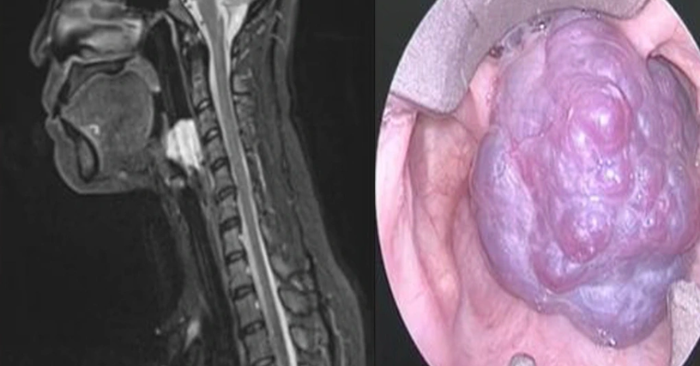

Tại Hội nghị Khoa học Đầu cổ châu Á – Thái Bình Dương (ASHNO 2025) diễn ra ở TP.HCM, bác sĩ Nguyễn Trương Khương, Giám đốc Chuyên môn Bệnh viện Đa khoa Quốc tế Nam Sài Gòn, đã thu hút sự chú ý của hàng trăm chuyên gia quốc tế khi trình bày ca phẫu thuật đặc biệt: u máu chiếm trọn thanh quản – một bệnh lý hiếm gặp đến mức y văn thế giới gần như chưa từng đề cập.

Bệnh nhân là chị A., 40 tuổi, sống tại TP.HCM. Hai tháng trước khi nhập viện, chị thường xuyên cảm thấy vướng họng, nghẹn khi ăn và khó thở. Ban đầu, chị chủ quan nghĩ chỉ là viêm họng hoặc rối loạn tiêu hóa nên tự mua thuốc uống. Khi triệu chứng ngày càng nặng, chị đến bệnh viện kiểm tra và được phát hiện có khối u máu lớn chiếm gần toàn bộ lòng thanh quản.

Sau khi thăm khám kỹ, bác sĩ Khương nhận định đây là ca bệnh cực kỳ hiếm: “Khối u máu phát triển trong lòng thanh quản khiến bệnh nhân khó thở, nói khó, nguy cơ tắc đường thở cấp tính bất cứ lúc nào. Y văn quốc tế cũng rất ít ghi nhận ca tương tự.”

Trước mổ, ê-kíp phải chuẩn bị kỹ lưỡng: ngừng thuốc chống đông 5 ngày, chủ động mở khí quản để đảm bảo đường thở an toàn. Trong nhiều giờ liền, các bác sĩ dùng dao siêu âm kết hợp đốt điện hai cực, vừa cắt bỏ khối u, vừa kiểm soát chảy máu và bảo tồn tối đa cấu trúc thanh quản.